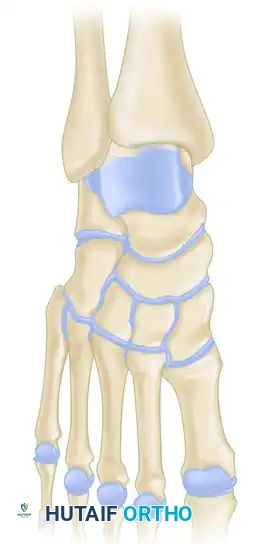

تصنيف أنواع الإصابات في مفصل شاركو

مخطط يوضح درجات وأنواع التشوهات في قدم شاركو